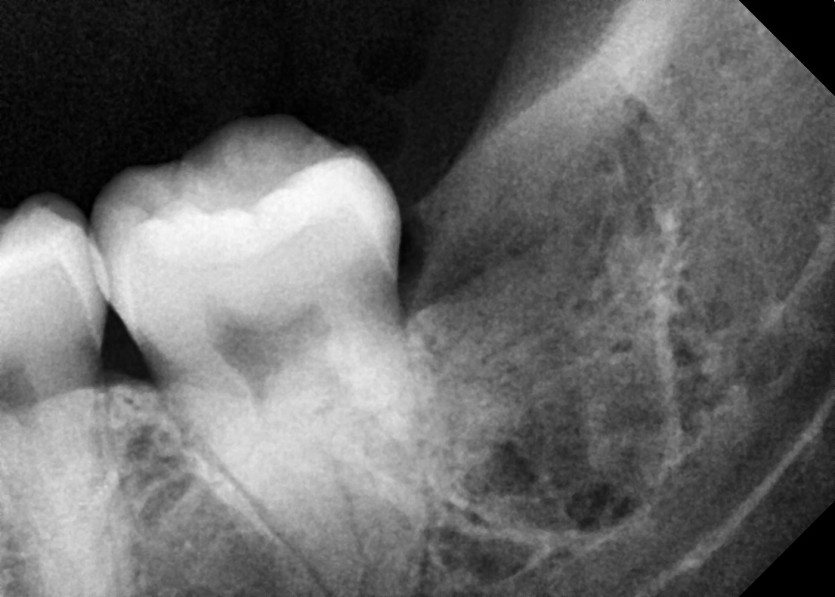

#38 사랑니 발치

구강외과 전문의가 당일 발치했습니다.